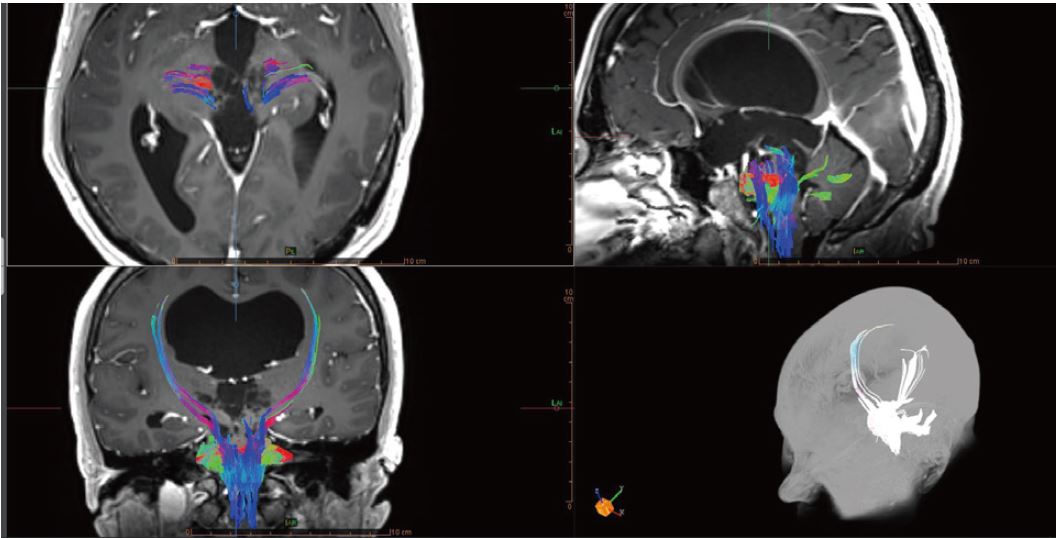

Завдяки дифузійно-тензорним картам (DTI) можна реконструювати та візуалізувати пучки нервових волокон і, таким чином, аналізувати вплив на останні інших розширень, особливо в середньому мозку (рис. 3).

Рисунок 3